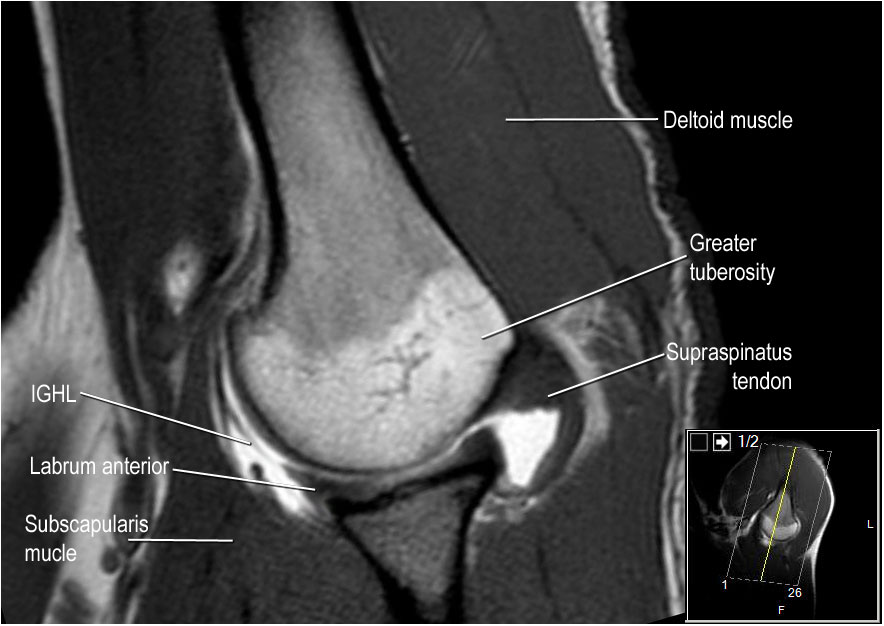

Hình ảnh mặt sau

Hình ảnh thể hiện các cơ và gân của cơ trên gai, cơ dưới gai và cơ tròn bé. Tất cả đều bám vào mấu động lớn.

Các cơ và gân chóp xoay có chức năng ổn định khớp vai trong quá trình vận động.